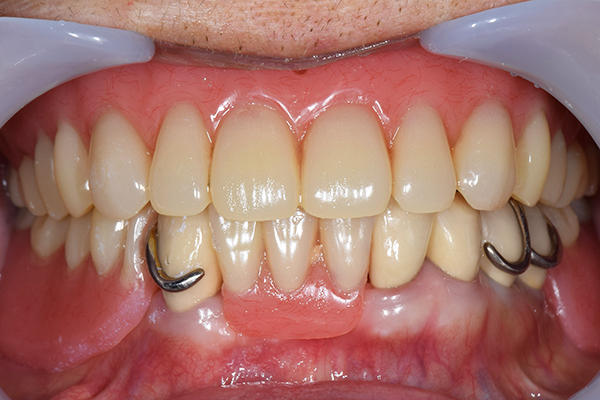

ケース1(自費の部分入れ歯)

前歯が折れて当院にいらっしゃいました。 過去に下の入れ歯を作ったが、合わなくなってずっと入れ歯をいれていらっしゃらない患者様でした。 これは奥歯で噛むことができないため、前歯で噛むことを繰り返したために、負担に耐えられなくなった前歯が折れてかぶせ物ごと 外れてしまったのだと考えられます。 痛くない、違和感の少ない、下の入れ歯を作ることがこの方のゴールであると考えられました。

金属を使用して、薄く違和感が少ない入れ歯が完成しました。 また、見た目にも気を使い、バネが見えにくい様な構造にしました。

入れ歯をお口の中にいれた状態です。前歯もMTMといって、歯を少し引っ張り出す処置を行なったことで、しっかり残せて、またかぶせ物をしました。

年齢 70歳・女性

主訴 前歯が取れた

治療期間 8ヶ月

治療費 .MTM:110,000円

.ファイバーコア:16,500円

.E-maxクラウン:110,000円

.義歯:660,000円

治療方針 長年使ってきた義歯の人工歯が磨耗し、臼歯部での咬合がすくなくなり、前歯部での接触が強くなったことで生じた前歯の破折なので、義歯も作り変える必要がある。

治療内容 前歯部MTMと同時に審美面の回復。

MTM中に義歯の作成も同時に行う。

最終的に義歯と前歯のクラウンを同時にいれる。

義歯は下顎で、しっかり噛めること、違和感の少ないものという希望があったため、なるべく入れ歯を薄く作成するために金属をしようした義歯とした。

また、見た目もあまり義歯が目立たない様に、バネの部分を見えにくいように作成した。

特記事項 歯にもともと入っていた金属の種類によっては、歯自体の変色を治療で変えられないこともある。 義歯は作ってから痛みがでることがありますが、それは調整を行うことで痛くなくすることができます。